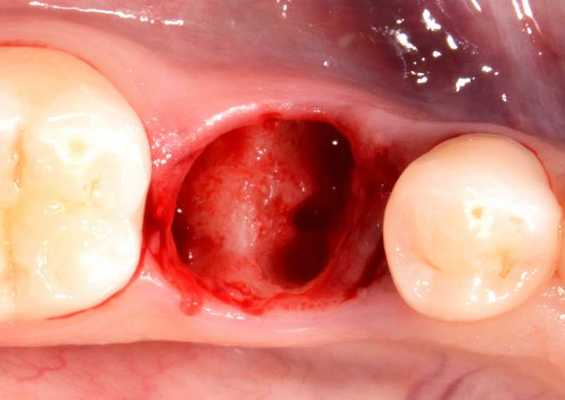

♦ Перфорация дна верхнечелюстной пазухи

Верхнечелюстная пазуха может быть двух типов: склеротического и пневматического. При склеротическом типе верхнечелюстной пазухи (малые ее размеры) она отделена от зубов толстым слоем костной ткани, который может быть нарушен развитием патологических процессов в кости (остеомиелит, кисты, опухоли и др.). При пневматическом типе верхнечелюстной пазухи последняя может располагаться очень близко от корней зубов (моляров и премоляров), отделяясь тонкой костной пластинкой, а иногда лишь слизистой оболочкой. В результате предшествующих патологических процессов, которые наблюдаются вокруг зуба, данная слизистая оболочка может быть плотно сращенной с периодонтом и повреждаться при операции удаления зуба, что может повлечь за собой возникновение носовых кровотечений.

Перфорация дна верхнечелюстной пазухи возникает как по вине врача (при травматическом или неправильном удалении зуба долотом, щипцами или элеватором, неосторожном обследовании лунки хирургической ложечкой или удалении грануляций с ее дна), так и в результате индивидуальных особенностей строения верхней челюсти (пневматический тип верхнечелюстной пазухи с низким расположением ее дна или предшествующими патологическими процессами в области верхушки корня зуба).

Прободение (перфорация) дна верхнечелюстной пазухи может произойти во время удаления верхних больших, реже - малых коренных зубов. Этому способствуют анатомические особенности взаимоотношения между корнями этих зубов и дном верхнечелюстной пазухи. При пневматическом типе строения пазухи верхушки корней больших и малых коренных зубов отделены от ее дна тонкой костной перемычкой. В области первого и второго больших коренных зубов толщина ее бывает 0,2-1 мм. Иногда верхушки корней этих зубов вдаются в пазуху и выступают над ее дном.

Перфорация дна верхнечелюстной пазухи может произойти и по вине врача. Это бывает при травматичном удалении зуба щипцами или элеватором, разъединении корней в области бифуркации долотом, а также во время обследования лунки хирургической ложкой, когда ее грубо продвигают вверх, пытаясь с усилием удалить грануляционную ткань со дна лунки

При удалении малых или больших коренных зубов сверху возможна перфорация пазухи верхней челюсти. Она характеризуется наличием сквозного отверстия в лунке. Состояние может сопровождаться кровотечением и отделением гноя. Важным этапом лечения считается контроль образования сгустка крови в отверстии при отсутствии воспалений. Чтобы ускорить заживление, на лунку помещают йодоформную турунду, гентамициновую губку или тампоном с противовоспалительным и анельгезирующим средством. Чтобы аппликации оставались на месте, их фиксируют пластмассовой капой или повязкой по типу лигатуры в форме цифры 8 на соседние зубы. Для прикрытия отверстия может использоваться съёмный протез.

Если образование сгустка не происходит, на лунке к краям десны закрепляется йодоформный тампон при помощи шелковых швов или каппы. Аппликацию нужно носить от 5 до 7 дней - за это время рана начинает затягиваться и необходимость в её дополнительном прикрытии отпадает. Важно правильно наложить тампон, чтобы он не заполнял полностью отверстие, в противном случае пациенту грозит воспаление синусов.

Если на дне пазухи обнаруживается отверстие значительных размеров, кровяной сгусток может не образовываться. Тогда стенки полученной лунки обрабатывают так, чтобы убрать все острые части, а затем ушивают без натяжения. При отсутствии положительного эффекта может проводиться наложение на отверстие биологического материала, после чего выполняется пластика дефекта мягкими тканями. Чтобы ускорить заживление, на рану накладывают йодоформный тампон, который фиксируют пластмассовой пластиной.